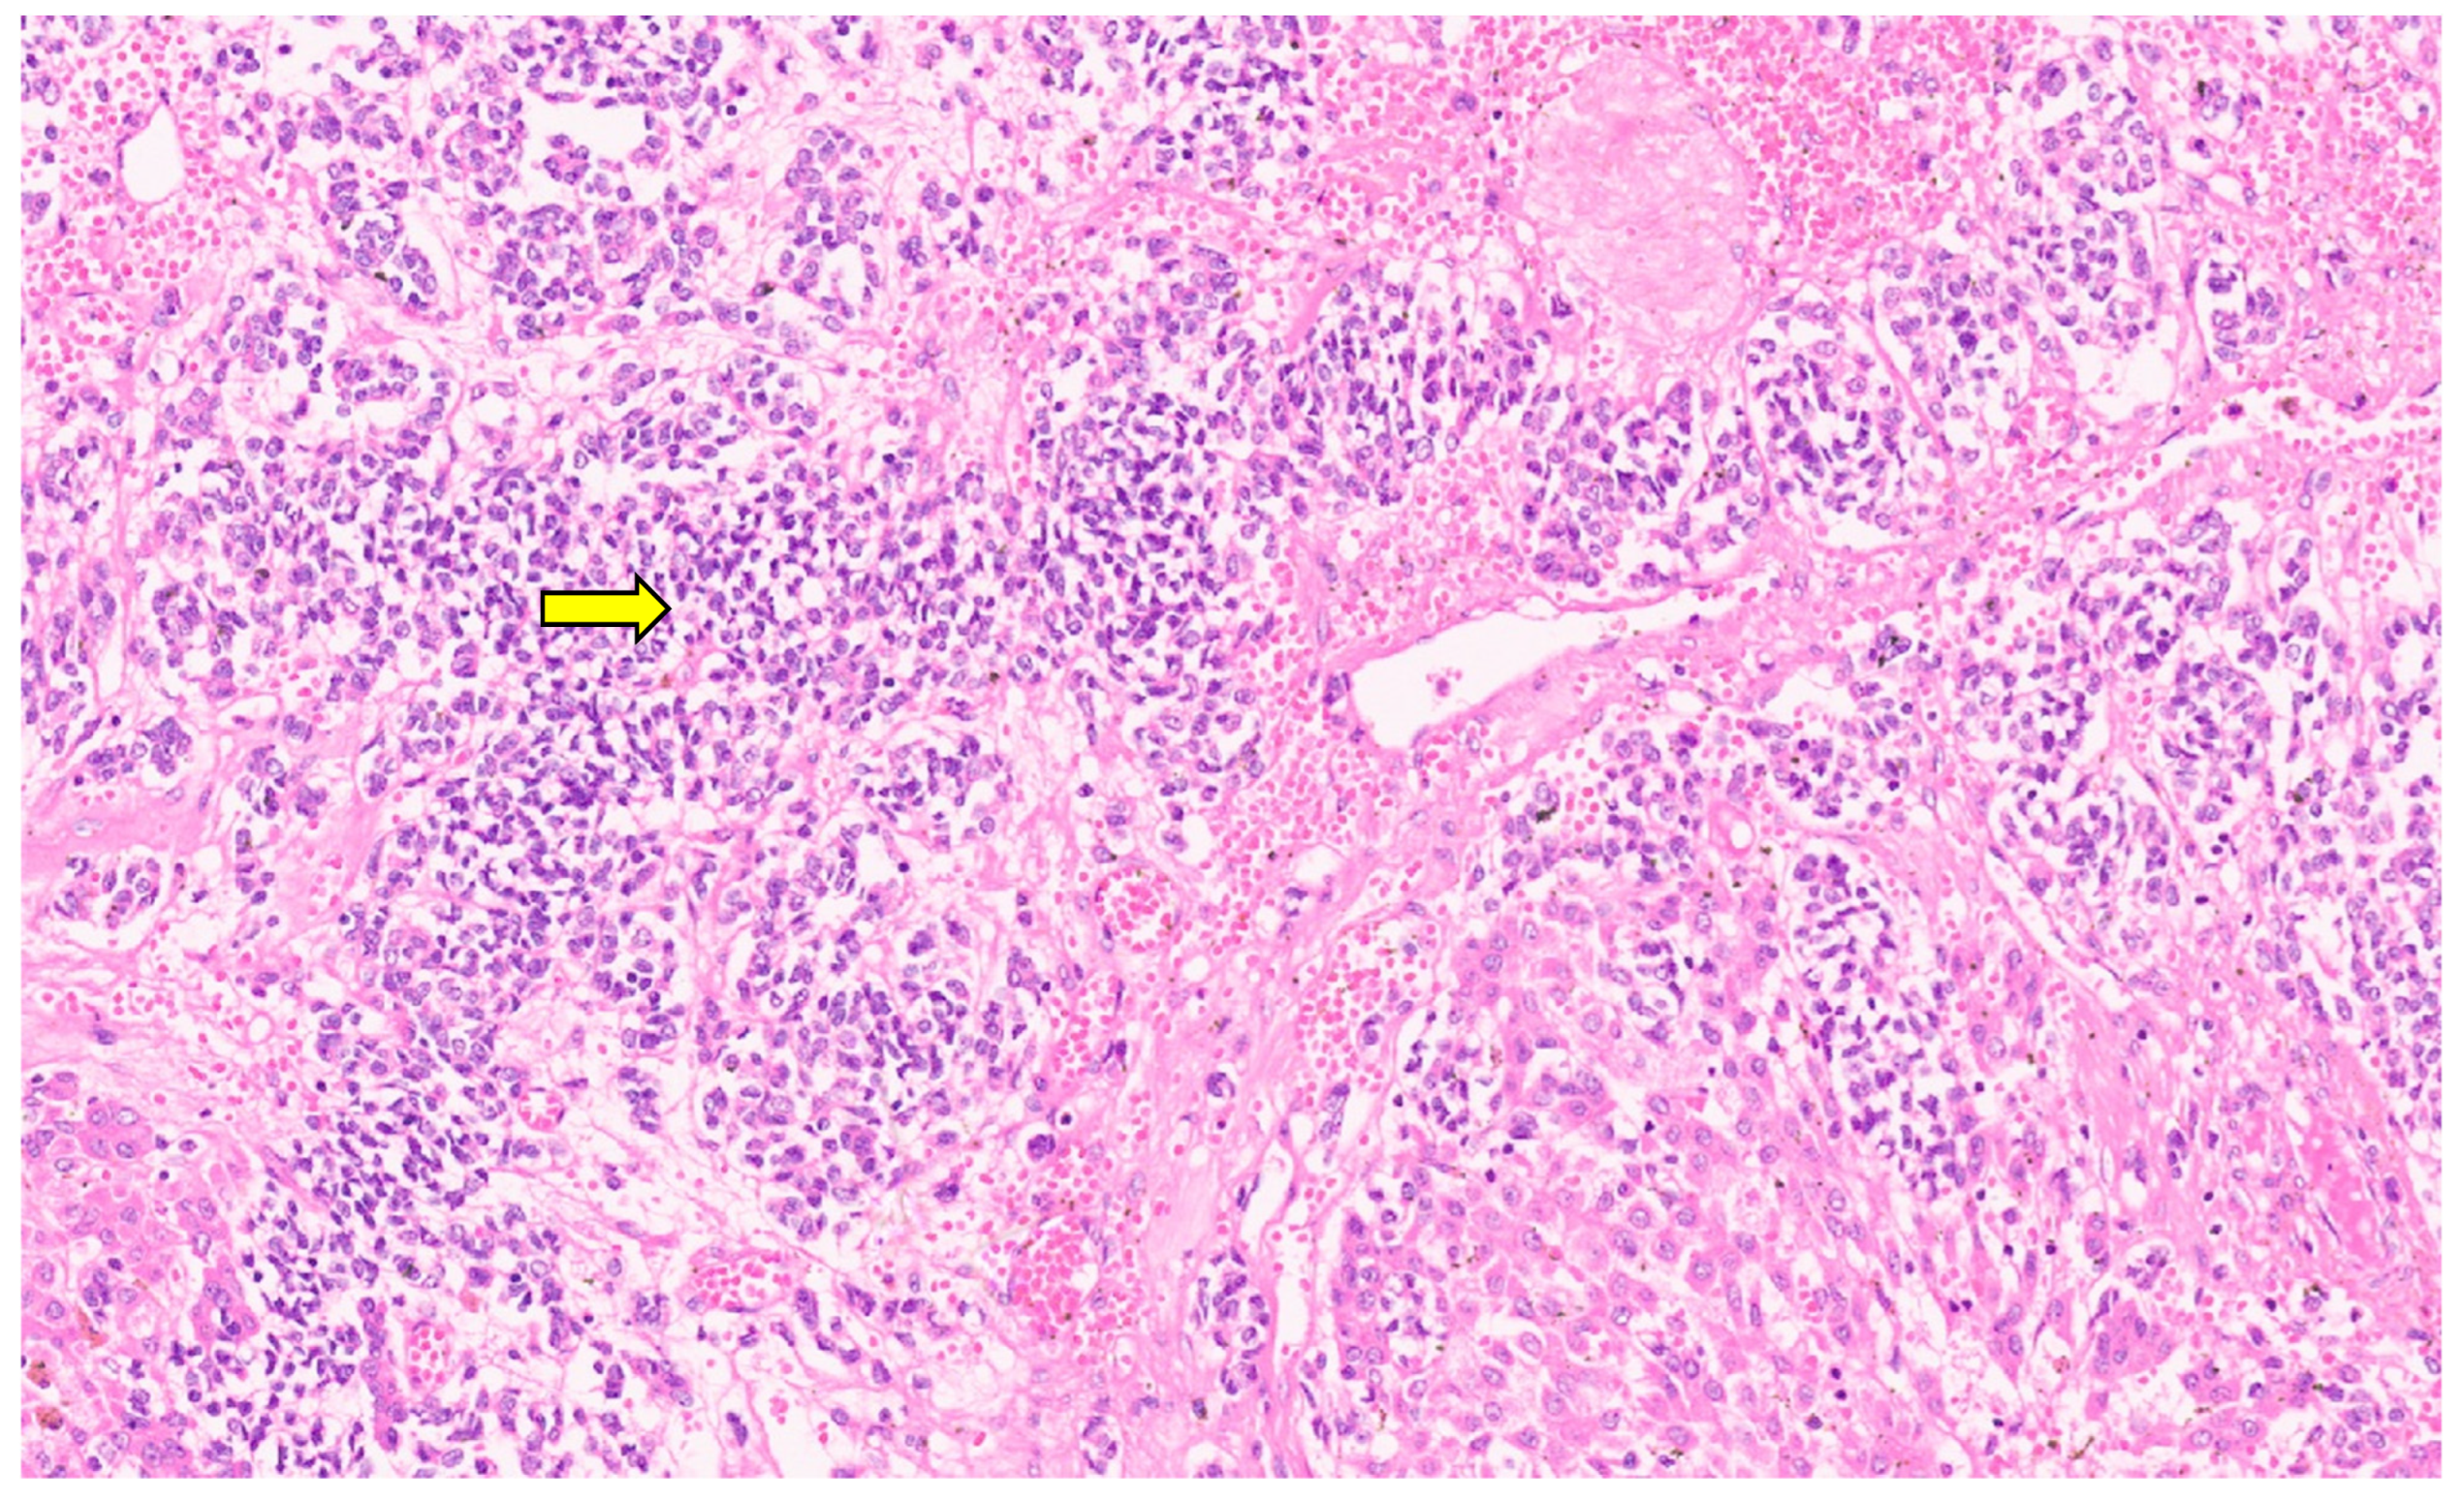

9.3. Pathology

10.3. Pathology